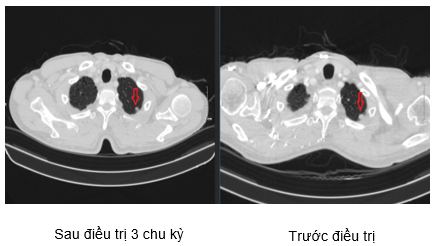

Hình 4. Hình ảnh khối u gan sau 3 chu kỳ điều trị: các khối u lớn nhất đường kính 22mm (hình bên trái) đã giảm kích thước so với phim trước điều trị (hình bên phải).

NHẬN XÉT: Như vậy chỉ sau 3 chu kì điều trị theo phác đồ Atezolizumab + Carboplatin + Etoposide, các tổn thương tại phổi, tổn thương di căn gan và các hạch khi được xác định trên các công cụ chẩn đoán hình ảnh đã có sự giảm kích thước đáng kể so với ban đầu, đồng thời khi định lượng CEA và Cyfra11-1 có xu hướng giảm từ sau chu kì thứ 3. Điều này chứng minh rằng phác đồ phối hợp trên là có hiệu quả đối với các bệnh nhân ung thư phổi tế bào nhỏ có di căn nhiều cơ quan như gan, hạch.